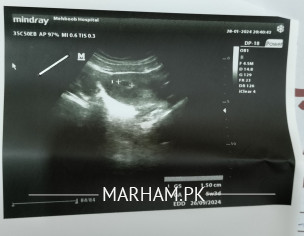

Asking For Self, Female 27, Rawalpindi

LMP 18.12.23 Pregnency test positive aaya hai Scan karvaya to doctor nai kaha weak hai boht growth ki medicine di hai injection bi lagaya hai. Agay ja kar koi masla to nahi hoga Any guide Report and medicine attach please help

Attach Photo here: